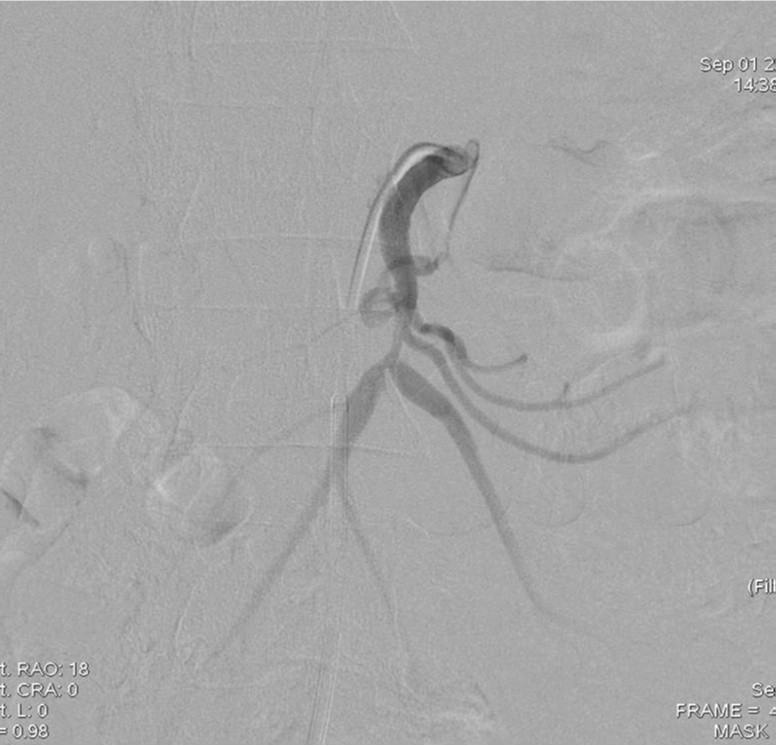

2009년 3월 복부 CT에서 SMA 기시부 하방 2cm 부위부터 5cm 길이의 편심성 혈전이 관찰되고 있으며 혈전이 있는 부위의 동맥 직경이 커져 있음(Fig. 1). 대동맥이나 분지 동맥에 동맥경화증의 소견은 관찰되지 않으며 심장초음파 및 심전도 검사에서 혈전이나 심방 세동은 없었음. CT 소견과 증상을 기준으로 spontaneous isolated SMA dissection으로 진단하였으며 창자의 허혈 소견이 보이지 않고 통증도 악화되지 않아 보존적 치료를 하였음. 2009년 6월 추적 CT에서 false lumen내 대부분의 혈전은 소실되었으나 SMA 기시부 5cm 하방 부위에는 국소적 혈전을 동반한 saccular pseudoaneurysm이 관찰됨. 2009년 8월 시행한 추적 CT에서 pseudoaneurysm의 직경이 2mm 증가함 (Fig. 2). 2009년 9월 시행한 혈관 조영술에서 saccular pseudoaneurysm이 SMA 기시부 5cm 하방부위에 관찰되며 SMA의 국소적 협착이 관찰됨 (Fig. 3). 스텐트와 코일을 이용한 혈관 내 치료 후 시행한 혈관 조영술에서 SMA의 국소적 협착과 pseudoaneurysm은 소실됨 (Fig. 4). 시술 3개 월 후 시행한 추적 CT에서 pseudoaneurysm은 완전히 소실되었으며 SMA는 정상소견을 보임(Fig. 5).

Fig. 3.

Fig. 3. Superior mesenteric angiography shows a saccular pseudoaneurysm with focal stenosis in the superior meseteric artery.